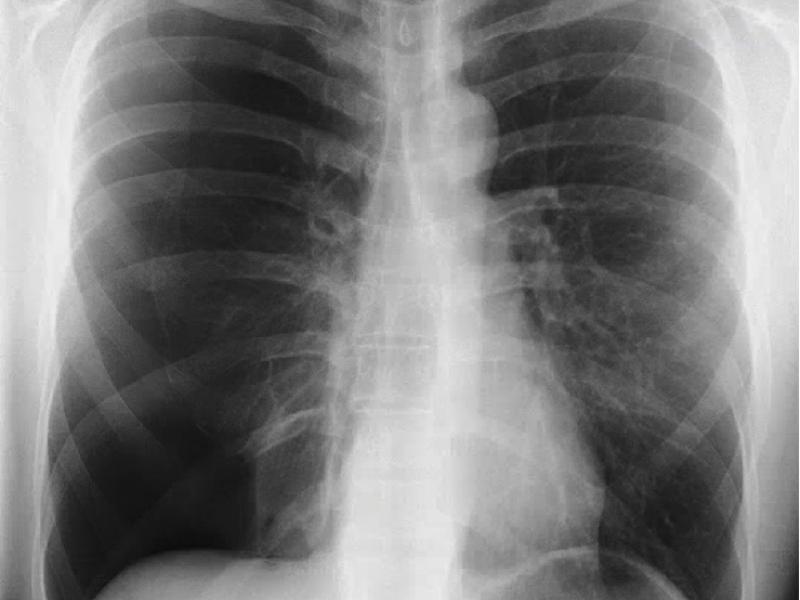

A 37 yo male with no sig PMH presents with pleuritic chest